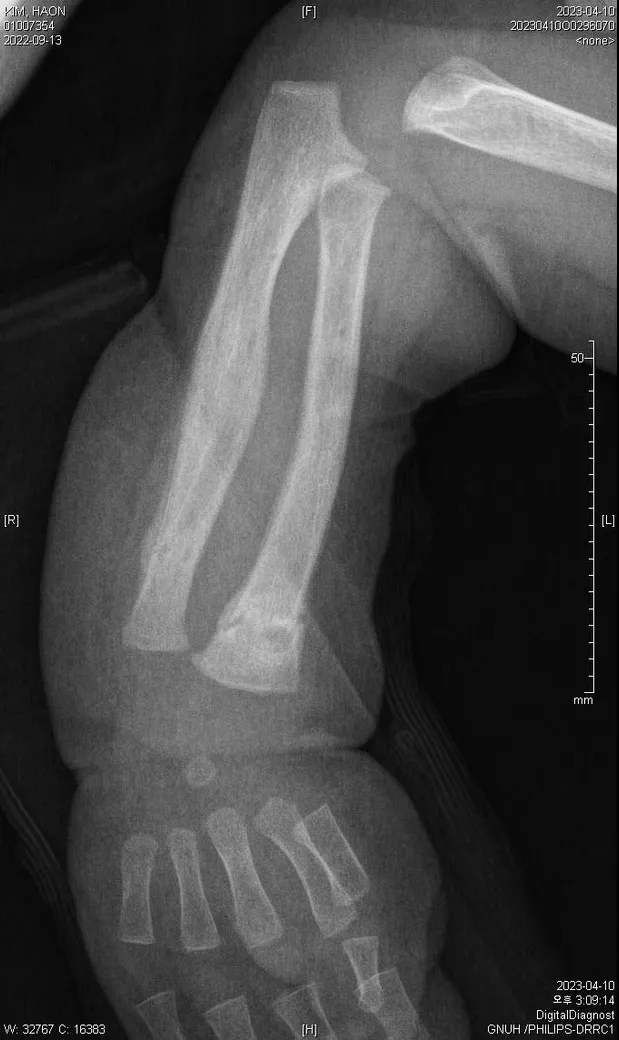

다름이 아니라, 첨부드린 엑스레이(X-ray) 사진처럼 골절 사실을 알게 되고 골절 발생 시점 대략적으로나마 추정시기를 파악하려고 문의 드리게 되었습니다

1) 3월 30일 촬영한 X-ray만으로 정확한 골절 시기를 100% 특정하는 데에는 한계가 있다는 점 충분히 인지하고 있기에 촬영날짜 기준으로 대략적으로 어느정도 시점에서 발생되었을 것으로 추측(ex 당일, 7~10일전, 7~14일 전, 10일 ~ 20일전, 14일 ~ 30일전 등등등)되는지 이해하고 싶습니다.

첨부드린 파일에도 있지만 4월 10일 사진에서는 유합 직전의 상당량의 켈로스 라는 것이 발견된다고 합니다.

• 1번 째 사진

보호자분이 원하시는 것은 2023-03-30에 골절이 된 사진만 가지고 언제 골절이 되었는지 추정을 하고 싶다는 말씀이죠? 3번째 사진에서 주변살들이 많이 부어있거나 하지 않아서 시간이 어느 정도 지난 것으로 보이네요. 초기유합은 1-2개월 정도 걸리는 것으로 알려져 있는 것으로 알려져 있으니 그 정도를 생각할 수 있을 것 같네요. 추정일 뿐입니다.